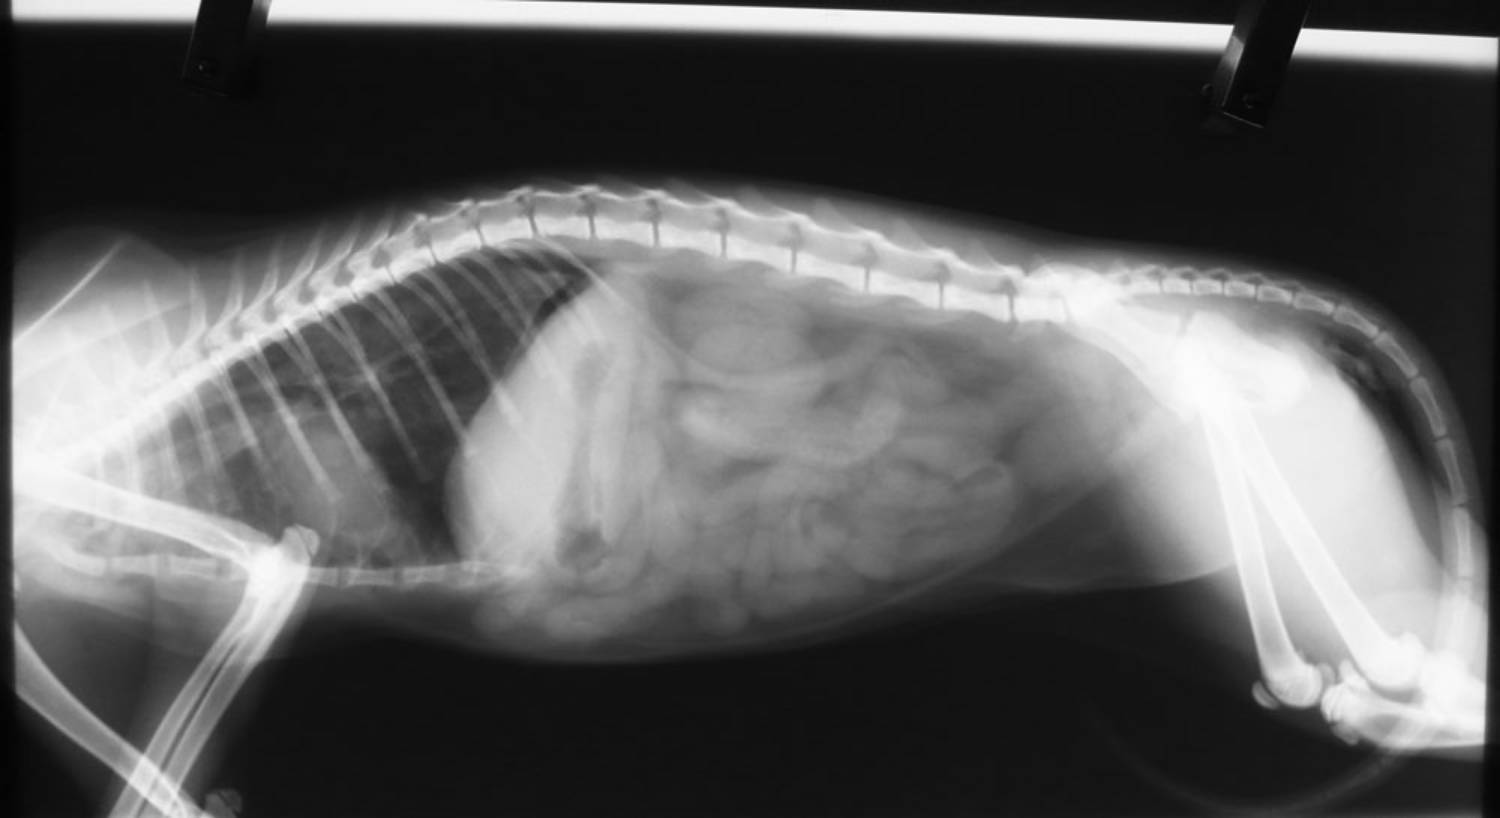

的醫助,到院後,發現貓很喘,嘴巴又都是血,先照X光,初步發現是助骨

斷了,胸腔出血,呼吸有困難,先住院,並提供氧氣,讓貓呼吸能順暢一點

,斷掉的肋骨,後來好的差不多了,突然開始吐,本來懷疑是胰臟炎,檢

查胰臟炎也是陽性的,但胰臟炎治療之後還是吐,做了造影劑檢查發現她的

腸道阻塞,後來開腹發現他的腸道有一段突然縮小,後來病理檢查是淋巴

性病變,推測是由之前外傷造成的,或許是因為被車子壓過去或撞到,導致

局部慢性發炎所致,開腹手術後,貓漸漸恢復了正常,待可出院時,將貓

接回照顧。